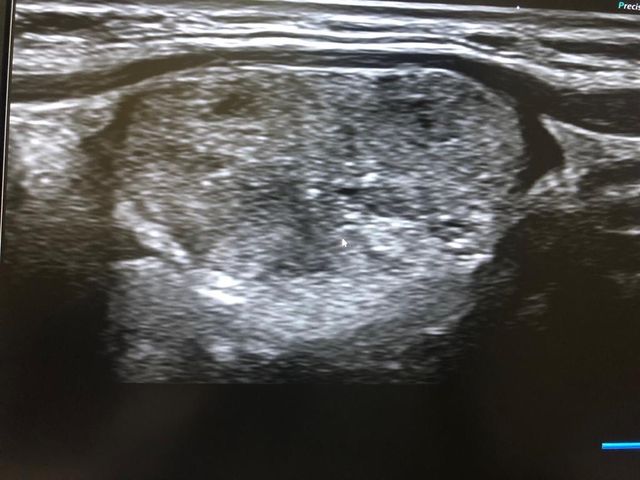

Picture for high-resolution ultrasound neck with expert radiologists give us more details Alzahra cancer center